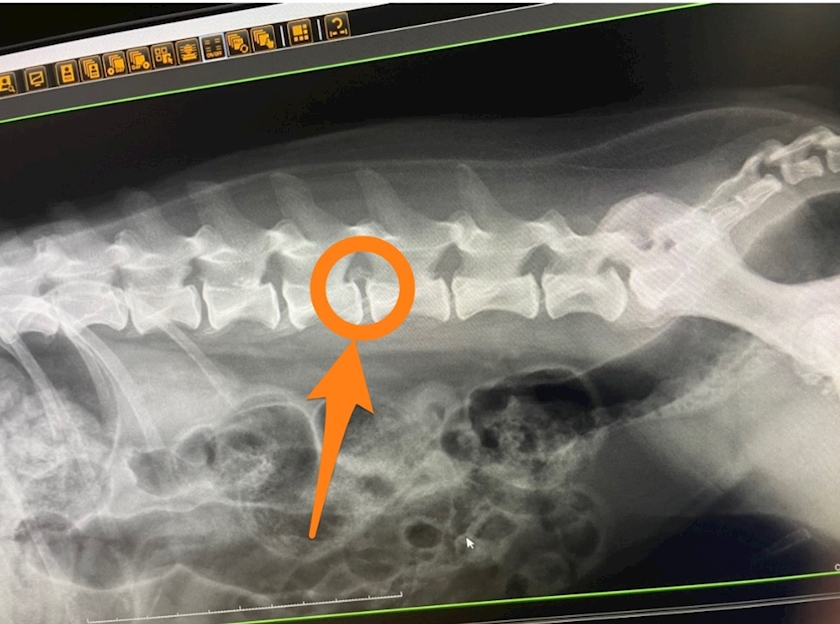

どうもここが

原因で歩けないらしい